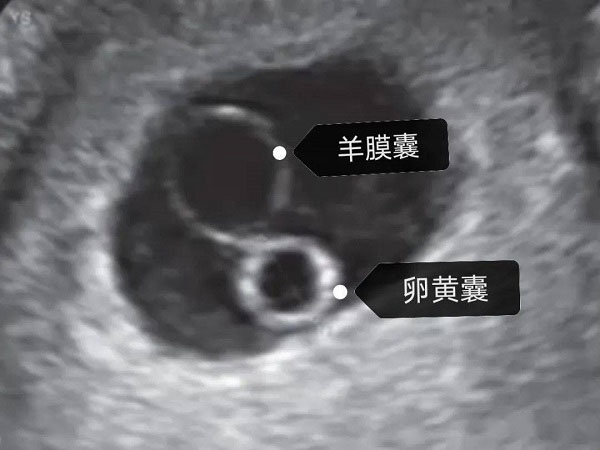

女性怀孕是一个非常复杂且辛苦的过程,为了进一步了解胚胎的生长发育情况,孕期都是需要进行B超检查的。一般来说,在女性怀孕5周左右的时候就能够看到胎心搏动和胎芽了。随着胚胎的逐渐发育,卵黄囊也会逐渐出现,并且会逐渐变大直到胎盘开始发育,才会逐渐消失。不同的孕周卵黄囊和胚芽的大小其实都是不同的,都有一个正常的范围值,具体的大家可以参照一下卵黄囊及胚芽孕周对照表。

卵黄囊和胚芽是女性怀孕之后胚胎逐渐生长发育而出现的,很多初次怀孕的女性对此并不是很了解。其实卵黄囊就是胚胎发生体褶后,原肠则明显地分成胚内的原肠和胚外的卵黄囊,内包有大量卵黄,卵黄囊的壁则是由胚外内胚层和胚外中胚层形成。

胚芽其实就是卵黄囊逐渐发育形成的,是卵黄囊中的原始细胞随着时间的增长,各细胞开始逐渐分化,慢慢就形成了胚芽,这是胚胎最初萌芽的阶段。随着胚芽的逐渐长大就会开始出现胎心搏动,这都是一个循序渐进的过程。

在怀孕之后女性都是需要定期到医院进行产检的,尤其是在怀孕初期的时候是需要通过B超检查了解胚胎是否成功着床的。通常情况下,在B超检查报告单中可见看卵黄囊及胚芽的话,那么就表示胚胎是在正常的生长发育的,大多数情况下在女性停经大概7周左右就能够通过B超看到。

卵黄囊就是我们常说的孕囊,卵黄囊和胚芽出现的时间其实是有区别的,一般在女性怀孕6周左右的时候就能够通过B超清楚的看到卵黄囊,在怀孕7周的时候就能够看到胚芽和胎心管搏动。当然因为胚胎的生长发育速度是不同的,因此也可能会有一定的推迟,但是最晚不会超过一周。